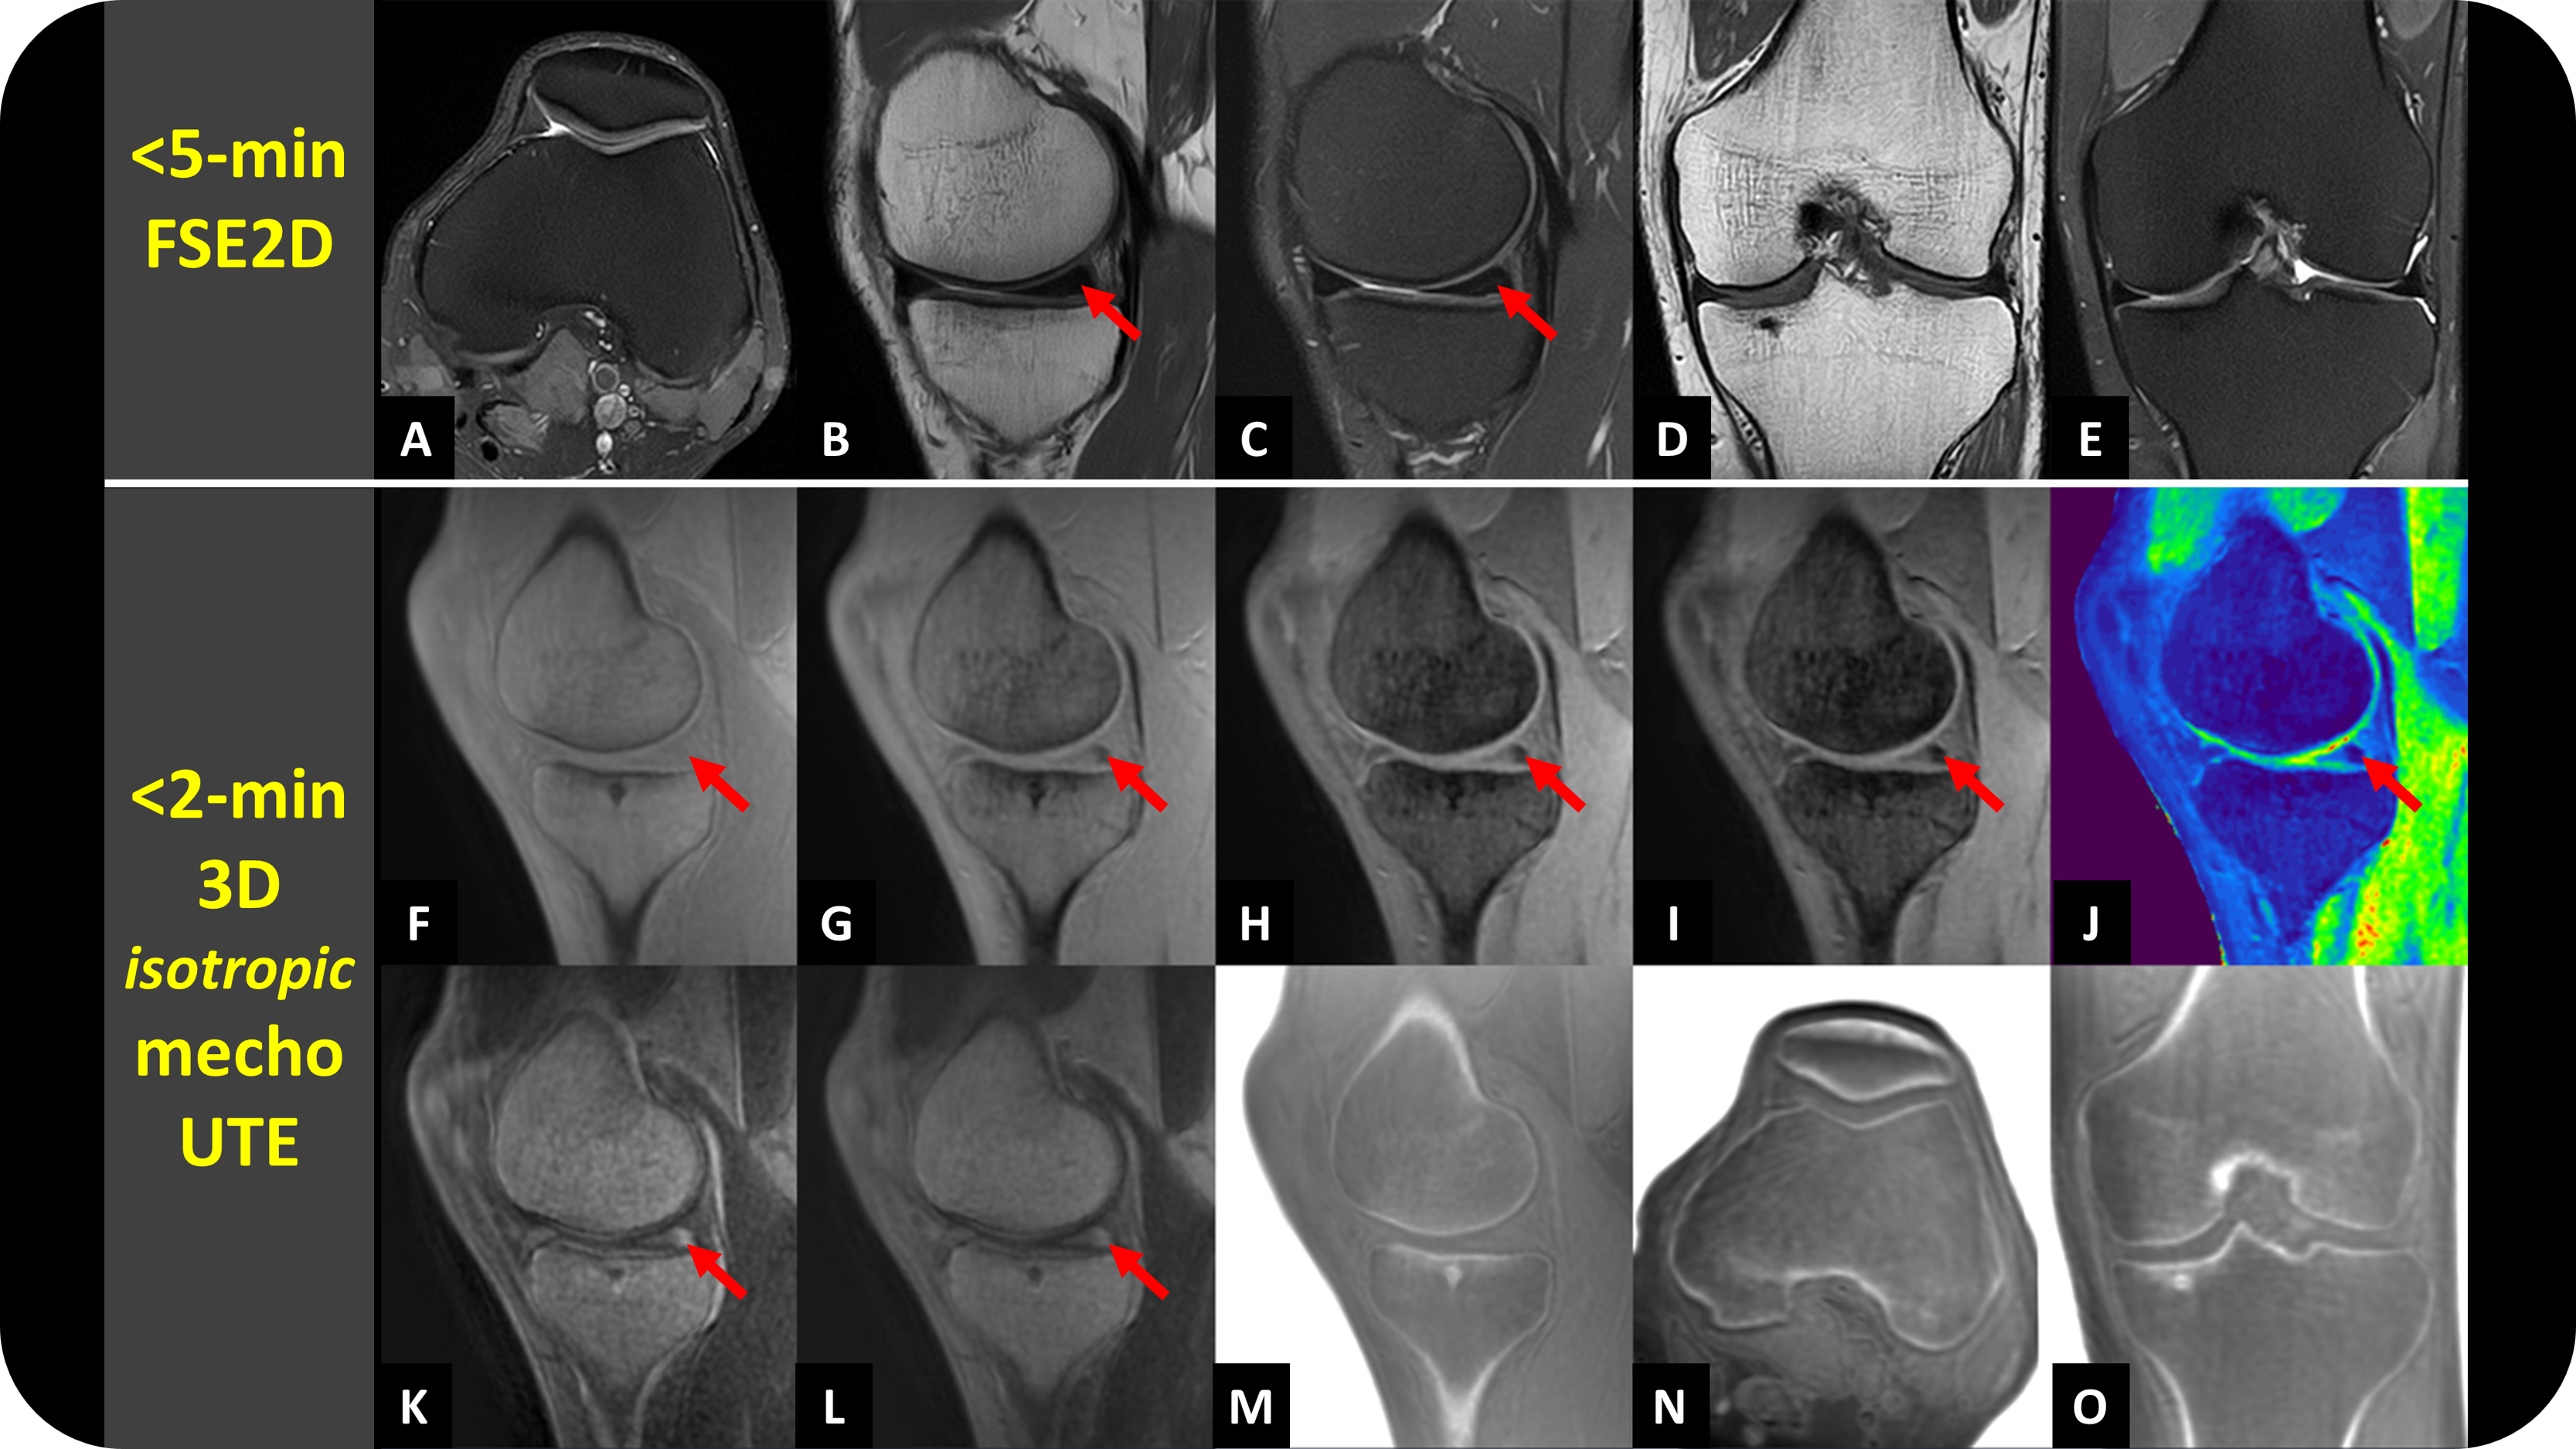

In this work, we demonstrate the feasibility of a fast, 2-minute multi-echo UTE acquisition that provides CT-like bone-weighted contrast and quantitative T2* mapping of short-T2 tissues. With the integration of deep learning-based reconstruction (MRI-DLR), routine MSK MRI can be completed in under 8 minutes. Together, this enables a comprehensive MRI-only MSK examination in under 10 minutes.

Total scan time can be further reduced by combining a 2-minute multi-echo UTE acquisition with an abbreviated musculoskeletal (MSK) MRI protocol, in which sequences are selected to maximize diagnostic yield per unit scan time. The abbreviated MSK-MRI protocol is indication-specific and can be completed in well under 3 minutes.

Together, this approach enables a comprehensive, MRI-only MSK examination in under 5 minutes. As a result, a single MRI-only exam can provide information traditionally obtained from both MRI and CT, while achieving CT-like throughput. This capability has the potential to position MRI as a first-line imaging modality, particularly by reducing or eliminating the need for subsequent MRI and/or CT examinations.